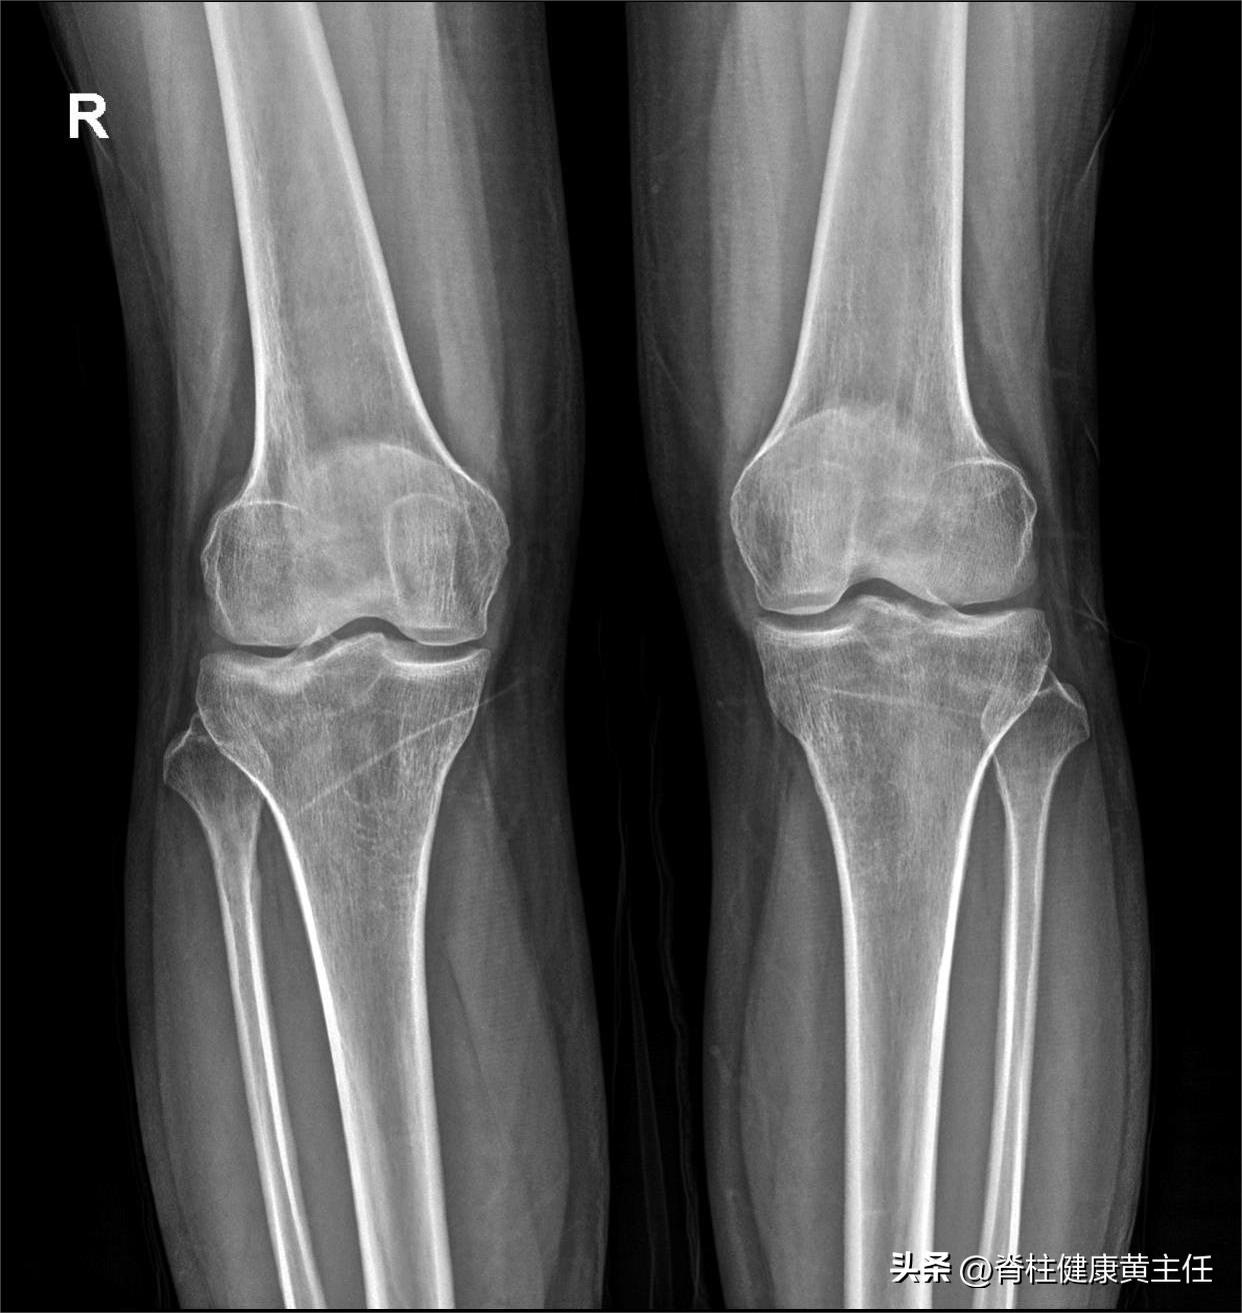

X光片检查

外院DR: 显示双膝轻微骨质增生,无明显异常。

腰椎、双膝X光: 腰椎小关节不稳,腰椎退行性变,双侧膝关节未见明显骨质异常。

正位片